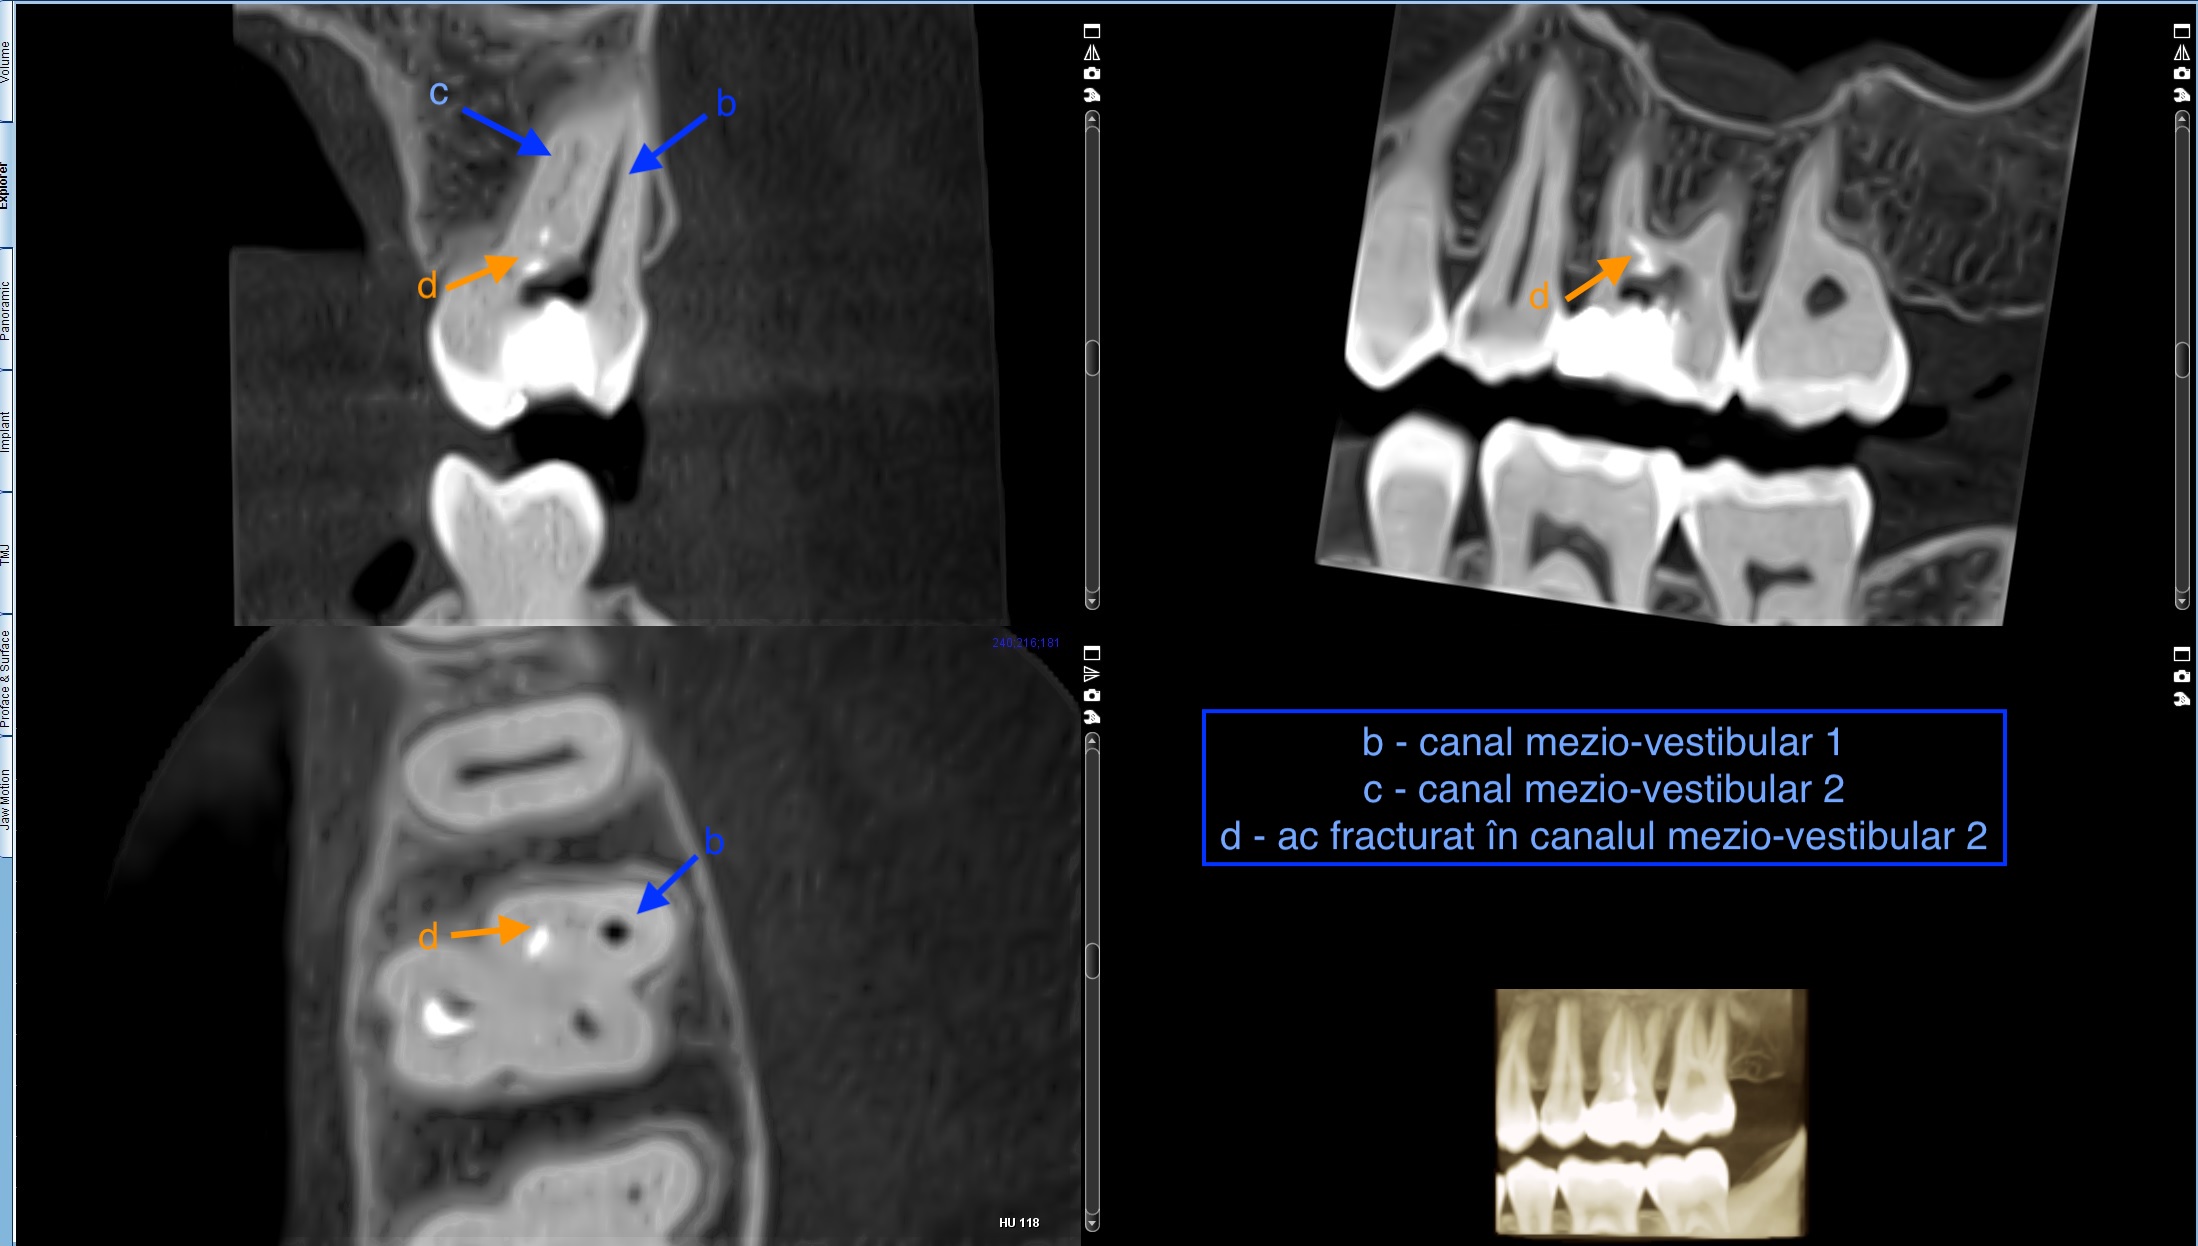

După ce s-a evaluat cu atenție cazul în clinica noastră, i s-a explicat pacientului că va fi nevoie de o radiografie tridimensională pentru a aprecia cu exactitate morfologia dintelui. La analiza radiografiei 3D am putut observa nivelul la care se afla perforația care urma să fie închisă (Figura 1) dar și nivelul la care s-a fracturat instrumentul rotativ (Figura 2).

Figura 2. Radiografia 3D prezentând nivelul la care s-a fracturat instrumentul